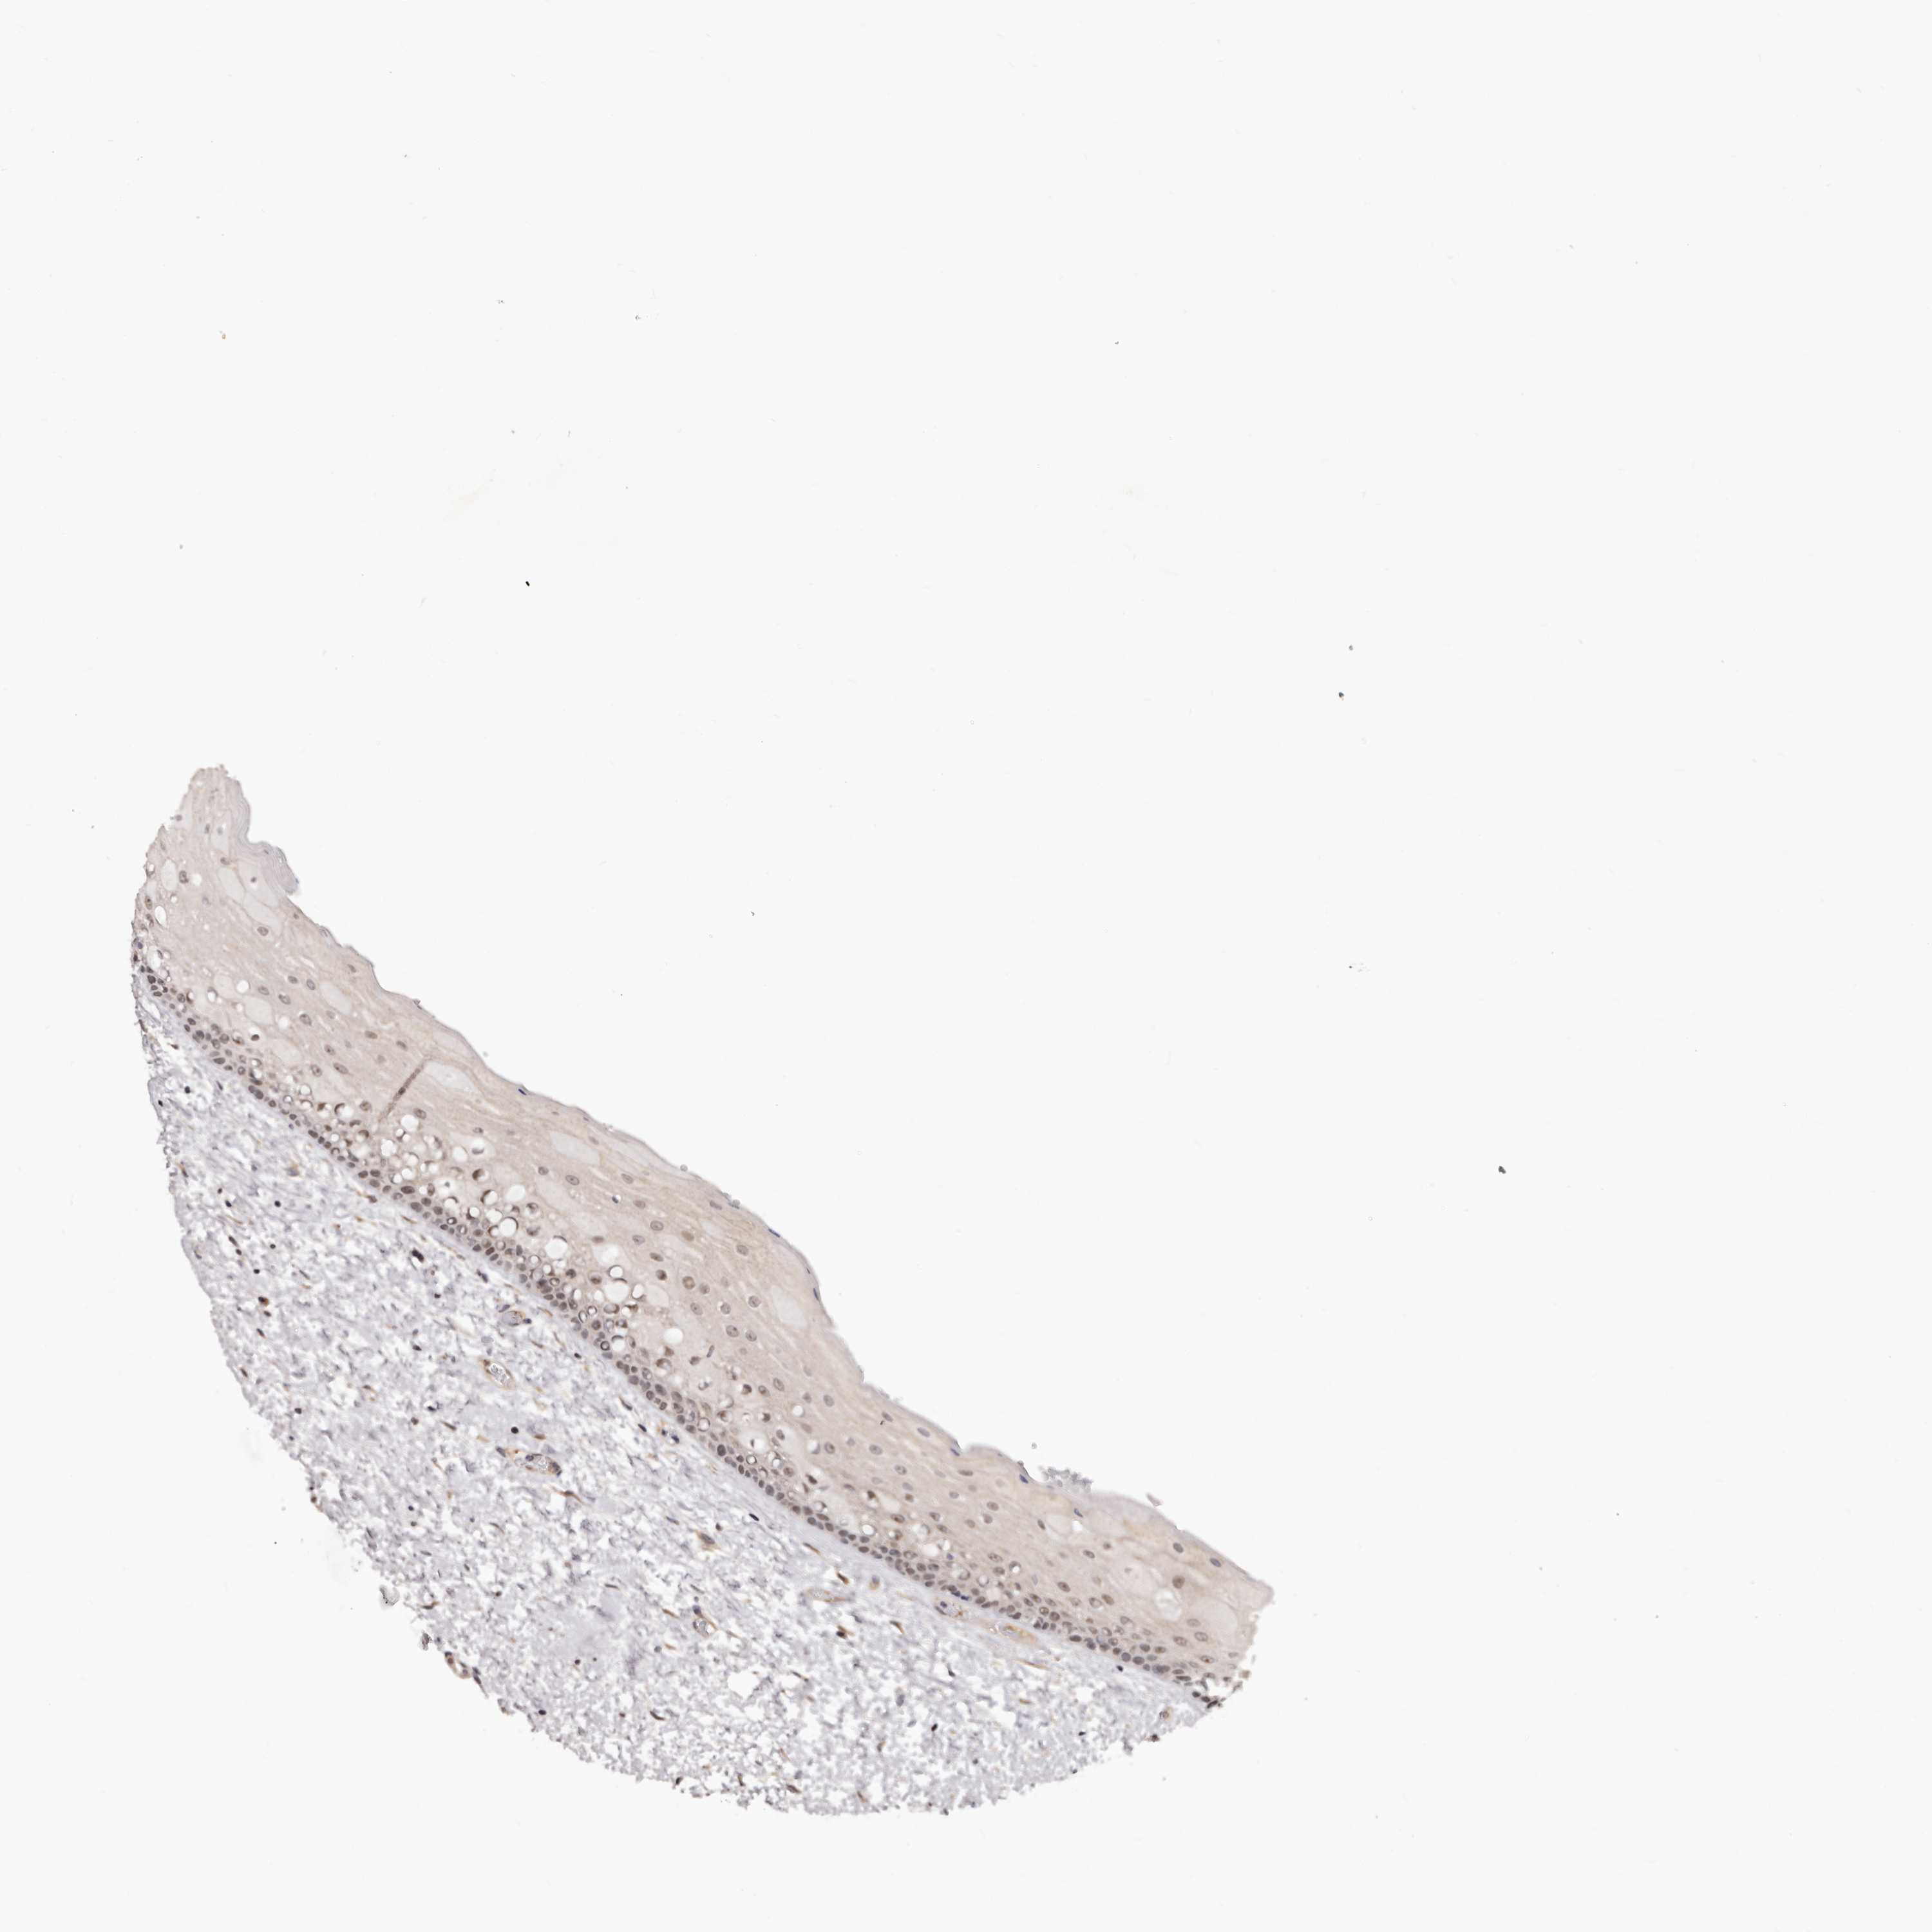

NOL12